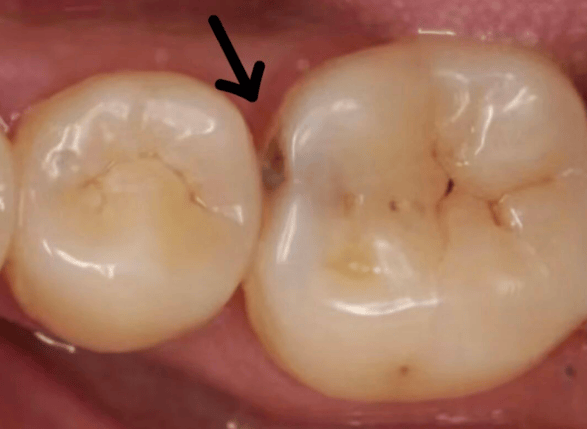

邻面龋

塞在牙缝里的食物残渣会被细菌分解产生酸性物质,腐蚀牙齿,造成邻面龋坏